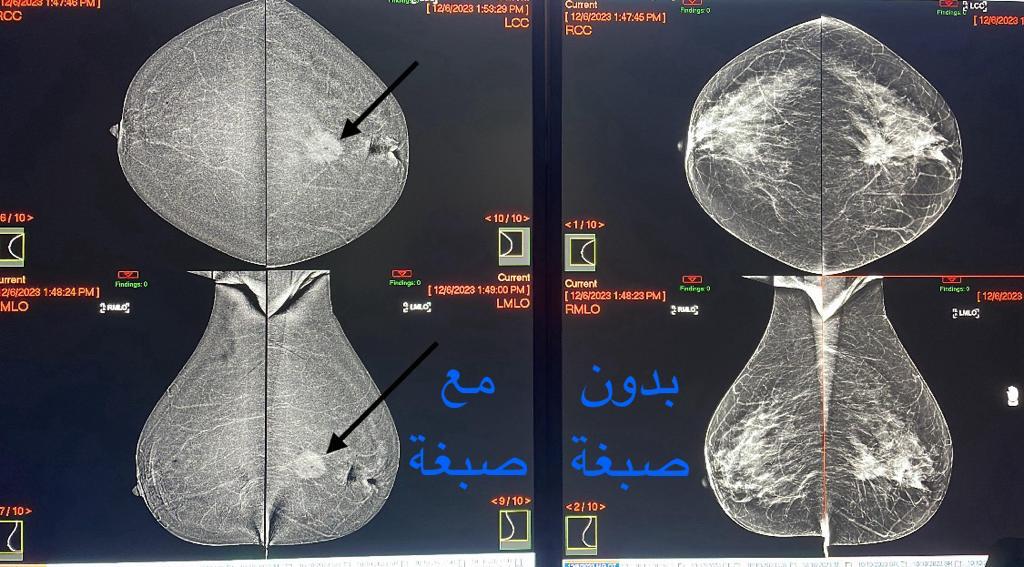

كشفت مدينة الملك سعود الطبية عضو تجمع الرياض الصحي الأول عن البدء بالعمل على تقنية جديدة و لأول مرة على مستوى المدينة والمتمثلة بتصوير الماموغرام بتقنية الصبغة (CEM) والتي تحمل وعدًا كبيرًا لإنقاذ الأرواح، وثورة في إدارة سرطان الثدي.

وأوضحت استشاري أشعة الثدي د.آلاء الحازمي بأن تقنية (CEM) تعد أداة حيوية في مكافحة سرطان الثدي، وذلك من خلال التغلب على قيود التصوير بالماموغرام التقليدي، وتعزيز قدرة الأطباء على اكتشاف وتشخيص الأورام الثديية بشكل أدق وأسرع، مما يساهم في تحسين النتائج العلاجية وسرعتها، وبالتالي زيادة الأمل في مكافحة سرطان الثدي.

وأشارت بأن التقنية تلعب دورًا حاسمًا في مراقبة استجابة المرضى للعلاج وزيادة خيارات الفحص للفئات ذات المخاطر العالية، مما يضمن الرعاية الشاملة ذات الجودة العالية.